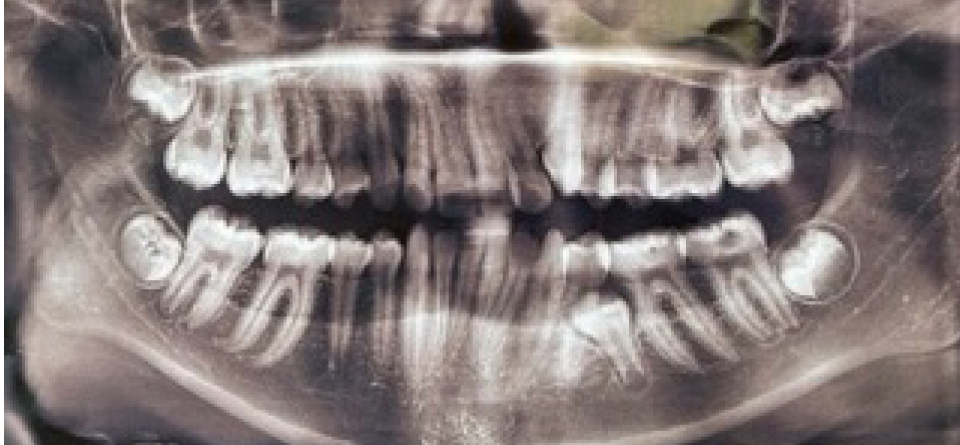

Результаты изучения анамнестических данных показали, что причиной односторонней ретенции вторых премоляров, как на верхней, так и нижней челюсти, было преждевременное удаление вторых молочных моляров на одной из сторон, которое отмечались практически у всех обследованных, что способствовало ретенции второго премоляра (рис. 2).

Рис. 2. Ортопантомограмма у пациентки с ретенцией второго нижнего премоляра слева

В связи с указанным фактом отмечалось перемещение зубов, ограничивающих дефект навстречу друг другу, что способствовало укорочению диагональных, передне-задних и трансверсальных размеров арки и изменению ротационных показателей зубов.

На стороне с ретинированным зубом отмечалось укорочение длины дуги в среднем по группе на (5,24 ± 1,29) мм. В связи с этим, как правило, отмечалось смещение центральной межрезцовой точки в сторону полудуги с ретинированным зубом по диагонали на (2,38 ± 0,61) мм, а по сагиттали, как правило, в язычную сторону – на (1,34 ± 0,57) мм. Отклонение диагональных размеров и смещение ключевых зубов относительно основных ориентиров, представлено в табл.